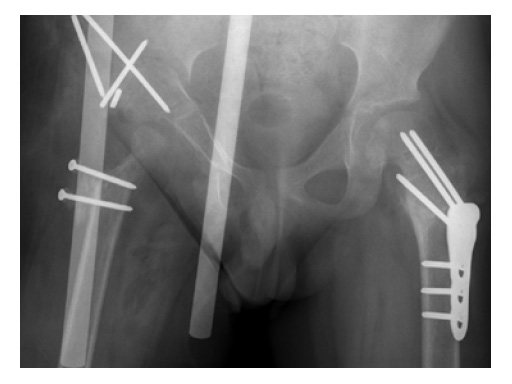

Case 2: LCP PHP 140. A 9-year-old boy, weighing 30 kg, had postinfectious pseudarthrosis of the femoral neck and varus deformity. His preoperative CC D angle was 80.

Case provided by Theddy Slongo, Bern, Switzerland